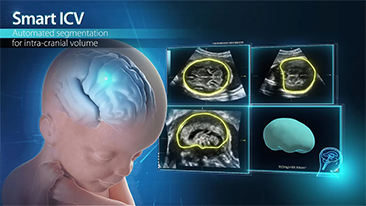

??? ??? ??? ???? ? ?? ???? ??? ? ?????

?? ?? ?? ??? ?? ?? ?? ???? ?? ???? OBG ?????? ?????. ?? ??, ?????(CNS) ??? ?? ?? ??? ?? ? ?????. ???? ?? ??? ?? ??? ??? ??? ?? MSP? 2D ????? ?? ???? ?????. ??? ?? ?? ? ??? ??? ???? ?? ???? ? ????.